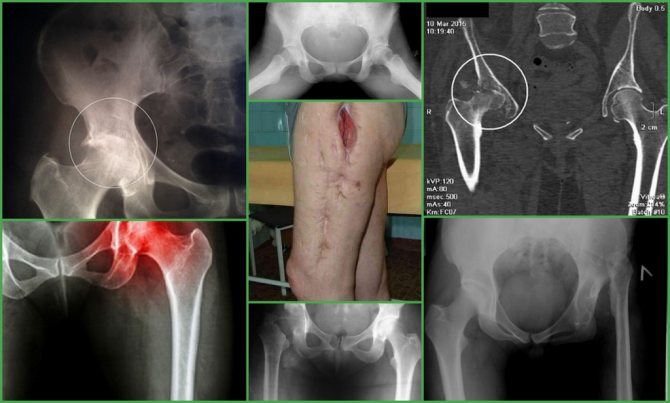

Условия для назначения протезирования сустава

Пациента после остеомиелита послать на замену сустава допустимо лишь в том случае, если одновременно выполняются 3 условия, огласим их.

- Рецидивов гнойного процесса не зарегистрировано в течение минимум 6 мес., в идеале – 2-х и более лет.

- Рентгенографические данные и результаты функциональной диагностики подтверждают необходимость замены сустава (коксартроз последних стадий, порочное положение сочленения, потеря опорных функций, ложный сустав, хромота, др.). Примите к сведению, что одного рентгена бывает недостаточно, поэтому может потребоваться пройти КТ и/или МРТ.

Далее назначаются рентгенография и компьютерная томография костей таза.

Диагностика остеомиелита таза

Современная инструментальная диагностика остеомиелита таза базируется на трех китах. Это радиоизотопная сцинтиграфия, магнитно-резонансная томография (МРТ) и компьютерная томография (КТ). Причем каждый из этих методов дополняет другой, а не является альтернативой. Остеосцинтиграфия наиболее информативна при остром гематогенном остеомиелите и обострении хронического. Уже с самого начала заболевания наблюдается повышенное накопление радиофармацевтического препарата (РФП) в очаге поражения, когда структурные изменения в костях еще отсутствуют. Трудно переоценить значение остеосцинтиграфии и при мультифокальном поражении скелета. Количественная оценка накопления РФП при хроническом остеомиелите позволяет объективизировать начало обострения патологического процесса.

Значимость КТ основывается на возможности детального изучения структурных изменений костей при хроническом остеомиелите: выявлении периостита, зон деструкции, секвестрации кости.

При остеомиелите шейки бедренной кости прогрессирующий некроз приводит к полному разрушению головки и шейки бедра. Если послеоперационный остеомиелит развился в ранние сроки после операции, на рентгенограммах видна линия перелома без признаков консолидации. В поздние сроки может определяться костная мозоль.